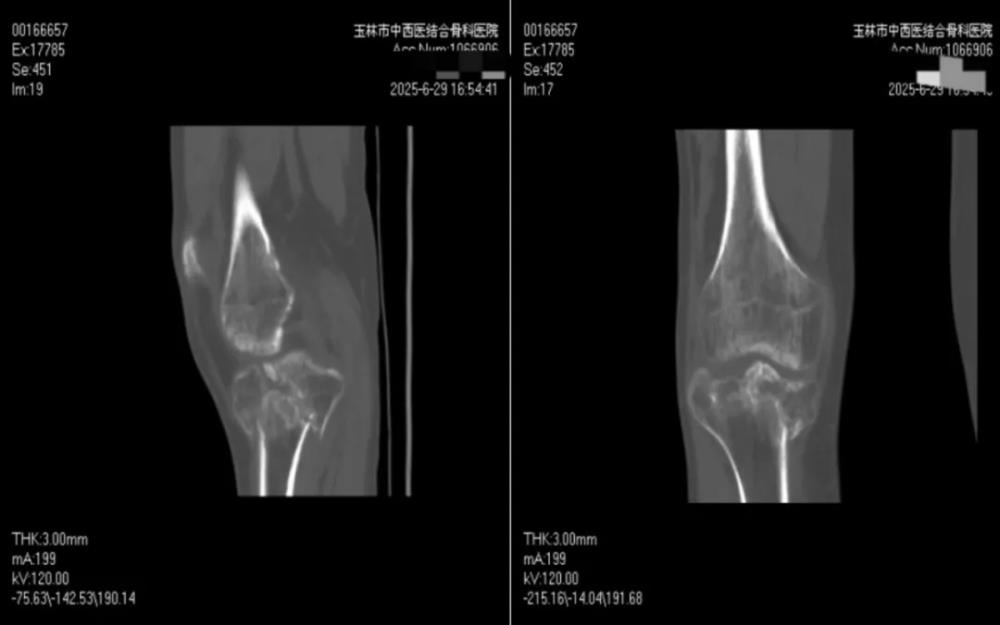

面对挑战,膝关节病与运动损伤科科主任黄丽雄所带领的膝关节运动与损伤科团队并未退缩,手术团队充分利用医院的3D临床打印中心”。这一创新平台,为罗某实施了个性化术前规划:将膝关节CT扫描数据导入软件,启动建立膝关节模板,使用MultipleSliceEdit模组编辑像素合集,对骨折块进行提取、分割及着色并转换为三维模型。在3D 对象窗口下,观察骨折的塌陷情况、移位距离及旋转角度,使用移动和旋转功能对各个骨块进行移动复位,将虚拟复位前、后的三维模型保存,经3D打印机等比例精准3D打印复制出患者受损的胫骨平台模型。这一技术犹如赋予医生一双“透视眼”,骨折线的走向、碎骨块的位移形态、关节面塌陷的程度等复杂情况在模型上清晰直观、一目了然。

依托这具高仿真模型,经科内严密讨论,反复推敲,最终确定了“膝内侧、外侧入路三钢板固定+植骨”的精密手术方案。这一清晰的规划,瞬间驱散了罗某心中积压已久的阴霾,使其重燃站立希望。